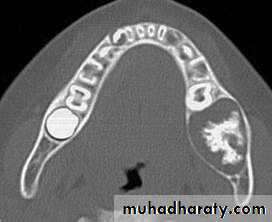

Cemento-ossifying Fibroma

Cemento-ossifying fibromas are rare fibro-osseous benign neoplasms that affect the jaws.Shape: — Round

— Monolocular.

Outline: — Smooth, well defined

— When opaque usually surrounded by a thin encapsulating radiolucent line

— Usually corticated and circumscribed.

Radiodensity: — Early stage — radiolucent

— Intermediate stage — radiolucent with gradually increasing internal radiopaque calcified patches

— Late stage — radiopaque zones coalesce to form a densely radiopaque mass with or without a radiolucent periphery.